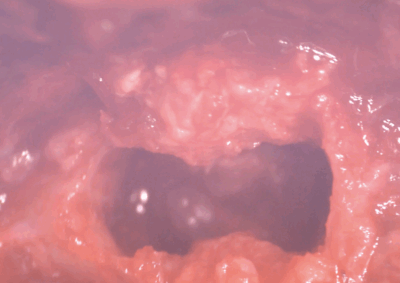

脳神経外科 注意 ボタンをクリックした先に、治療中および手術中の画像が説明で使用されている場合がございます。 そのような画像に弱い方は閲覧なさらないようお願いいたします。 脳神経外科 セメントレス環軸固定術 脳神経外科 Hemi-Laminectomy 脳神経外科 Ventral Slot 脳神経外科 椎体固定術 脳神経外科 Hemi-Laminectomy 脳神経外科 脊髄亜膜下憩室切除 脳神経外科 椎間板ヘルニア G1 脳神経外科 椎間板ヘルニア G2 脳神経外科 IVDD G5 脳神経外科 Ventral Slot 脳神経外科 Ventral Slot 脳神経外科 Ventral Slot 123456> 症例カテゴリー 放射線治療整形外科軟部組織外科脳神経外科内科腫瘍外科救急・集中治療リハビリテーション科腫瘍内科内視鏡科脳神経科呼吸器外科中医・漢方猫の腎移植循環器科電気化学療法